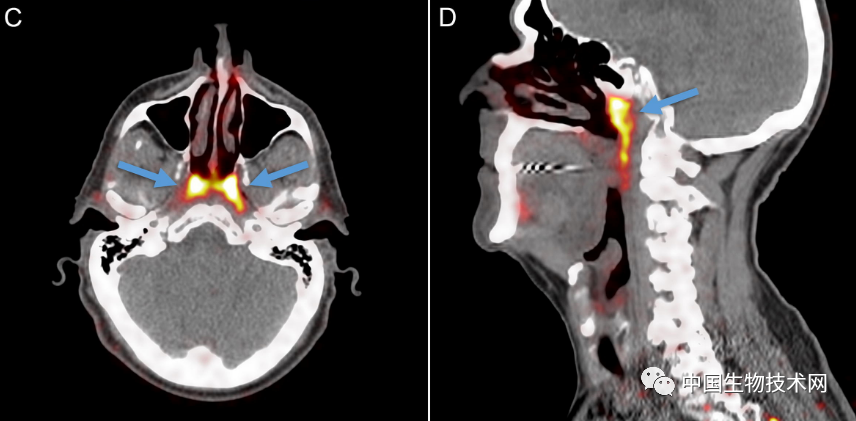

在对所有100例患者进行的PSMA PET/CT扫描 , 均发现存在这些管腺 , 并且对两名尸体(一男一女)的身体检查也显示出神秘的双侧结构 , 从宏观上可见引流管开口朝向鼻咽壁 。

研究人员在他们的论文中解释道:“据我们所知 , 这个结构并不符合之前的解剖学描述 。 据推测 , 它可能含有大量的浆液腺泡 , 对鼻咽/口咽润滑和吞咽起到生理作用 。 ”

至于这些腺体是如何被识别出来的 , 研究人员表示 , “管状腺”是在颅底一个不易接近的解剖位置被发现的 , 用内窥镜是很难辨认出来的 , 因为它们是一个更大腺体系统的一部分 。 此外 , 只有更新的PSMA-PET/CT成像技术才能检测到新唾液腺的结构 , 这超出了超声波、CT和MRI扫描等技术的可视化能力 。